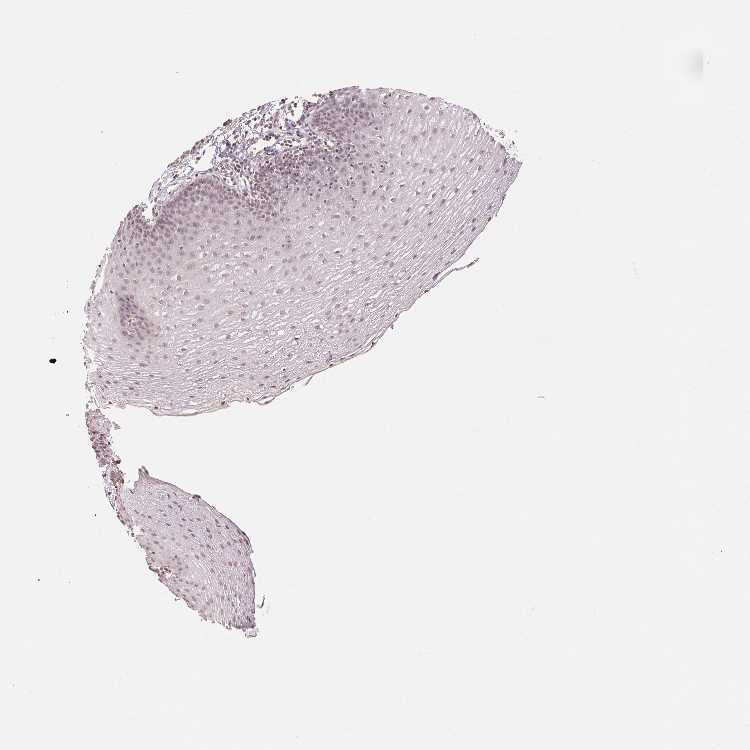

ESOPHAGUS - Antibody stainingi

Antibody staining in the annotated cell types in the current human tissue is reported as not detected, low, medium, or high, based on conventional immunohistochemistry profiling in selected tissues. This score is based on the combination of the staining intensity and fraction of stained cells.

Each image is clickable and will lead to virtual microscopy that enables deeper exploration of all samples and also displays staining intensity scores, fraction scores and subcellular localization as well as patient and tissue information for each sample.

Antibody HPA049805

Squamous epithelial cells Low